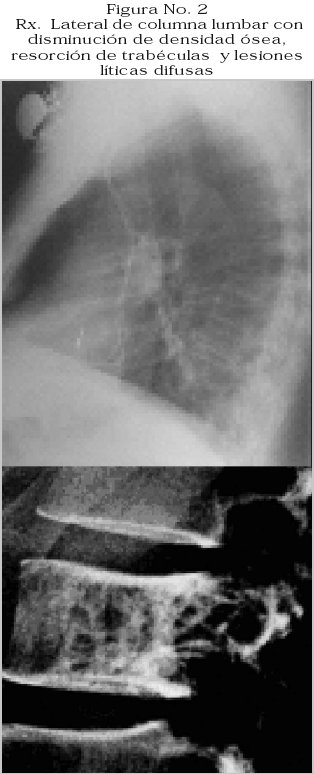

La radiografía de columna lumbosacra informa disminución de densidad ósea, lesiones líticas difusas y acuñamiento vertebral, Figura No. 2.

Por tomografia axial computarizada (TAC) se evidencia canal vertebral estrecho, protrusiones discales L4-L5, L5-S1, con resorción de trabéculas en cuerpos vertebrales.